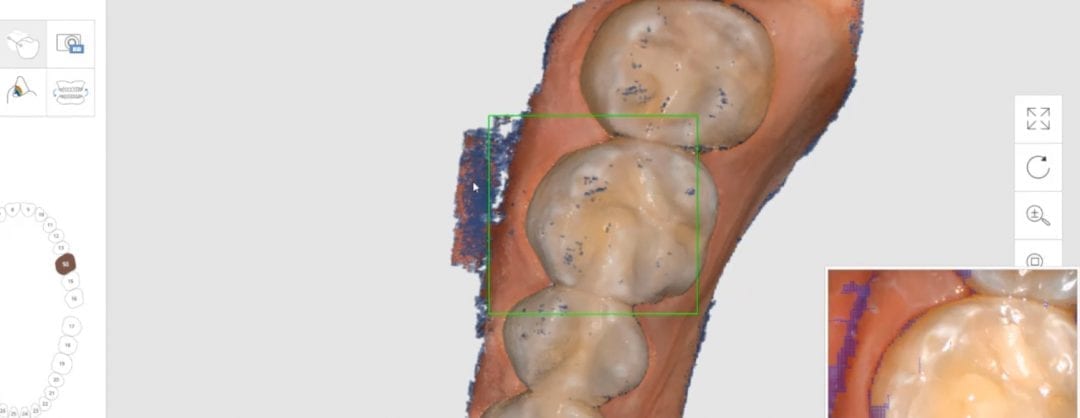

August 1, 2018In this particular clinical case, the patient has opted to utilize clear aligners to straighten some anterior crowding. The Medit i500 was used to capture both the upper and lower […]